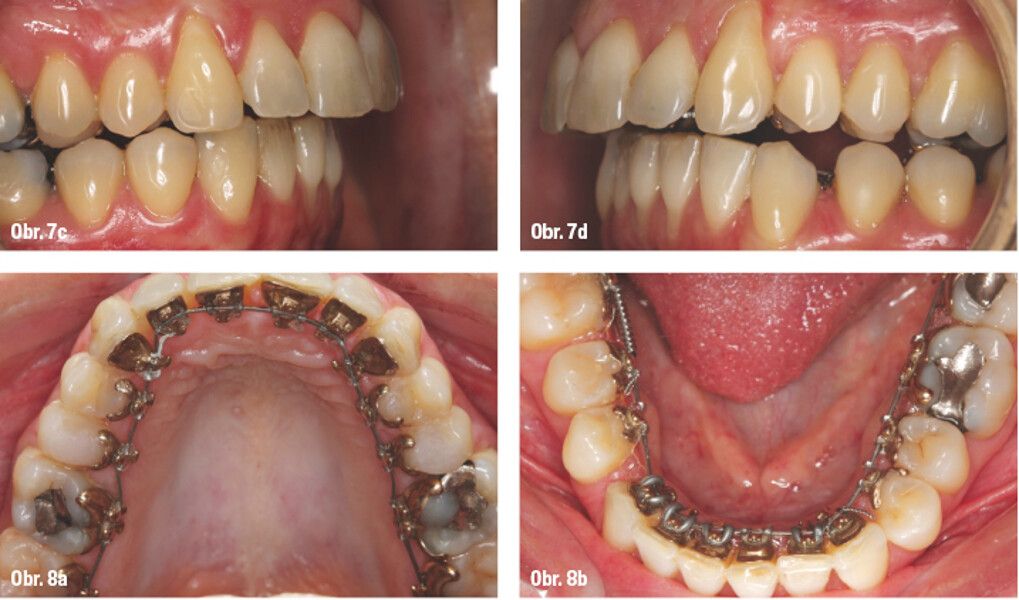

Lingvální zámky 3M™ Incognito™ System a kombinovaná ortodontickochirurgická terapie